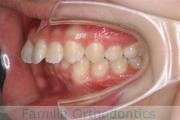

上顎

下顎

前歯の関係など

右側

正面

左側